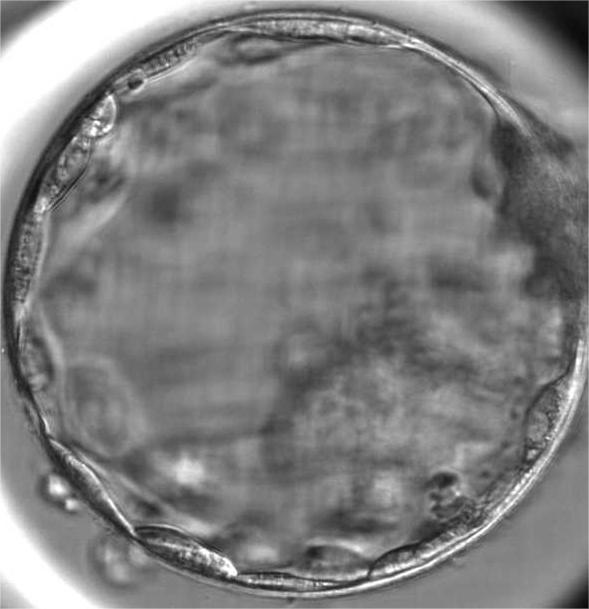

标题:Reproductive outcomes of artificial oocyte activation after ICSI in patients undergone blastocyst transfer: a 6-year retrospective cohort study